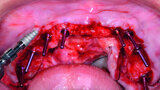

Fig. 13: Mandibular arch anaesthetised.

Fig. 14: Mandibular surgical guide stabilised.